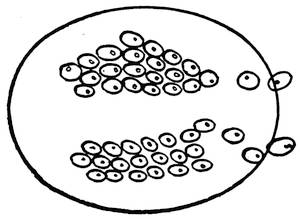

The ovum or even the zygote (i. e., the impregnated ovum) is a single-celled organism and resembles the animals of the first or lowest type in the animal kingdom. The protozoa are nothing else than single-celled animals. Some of them have even a lower structure than the common cell. The Monera, e. g., has neither nucleus nor membrane. The manifestations of life are recognizable only by the possession of the faculties of the assimilation of food and of propagation by segmentation and division.

Like the protozoon, the ovum, immediately after its impregnation, begins to undergo a certain division, by a series of successive segmentations, into 2, then 4, 8, 16, 32, 64, etc., cells. By continuous cell segmentations a great mass, the morula or mulberry, is produced. The structure of the morula corresponds with that of the coelenterata, or the animals of the second type. To this type belong the animals with gemmiparous reproduction, or multiplication by means of buds. The divided animals remain together and form colonies, as e. g. in sponges or corals.